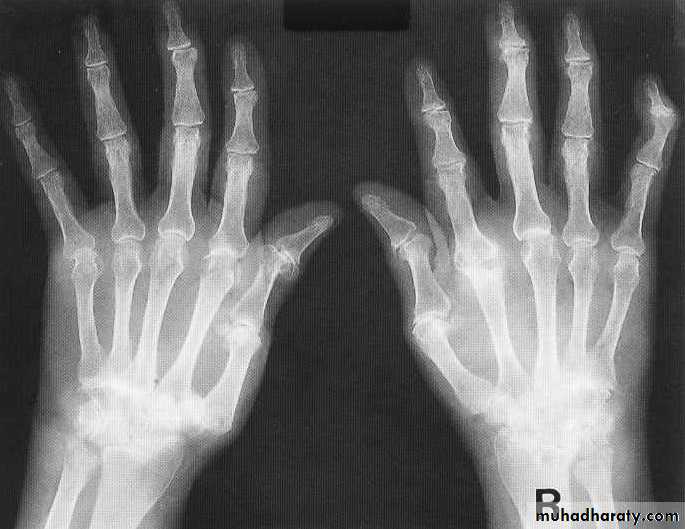

RHEUMATOID ARTHRITISFema1e:male = 3:lRadiographic features

Early changes

* Peri articular soft tissue swelling (edema, synovial congestion)

*Peri articular osteoporosis in symmetrical distribution (hallmark)

* Preferred sites of early involvement

Hands: 2nd and 3rd MCP joint

Feet: 4th and 5th MTP joint

Late changes

*Erosions (pannus formation, granulation tissue) first attack joint portions in which protective cartilage is absent (i.e., capsular insertion site).

* Erosions of the ulnar styloid and triquetrum are characteristic.

* Subchondral cysts formation results from synovial fluid, which is pressed into bone marrow through destroyed cartilage.

Subluxations , Carpal instability and ulnar deviation .

* Fibrous ankylosis is a late finding.

• Rheumatoid arthritis. Bilateral changes are fairly symmetrical. Soft-tissue swelling is demonstrated, especially over the ulnar styloids. Erosions are demonstrated at the carpus, distal radius and ulna, with joint space narrowing and collapse of bone. Metacarpophalangeal erosions are also seen associated with joint space narrowing. There is a swan-neck deformity of the right fifth distal interphalangeal joint